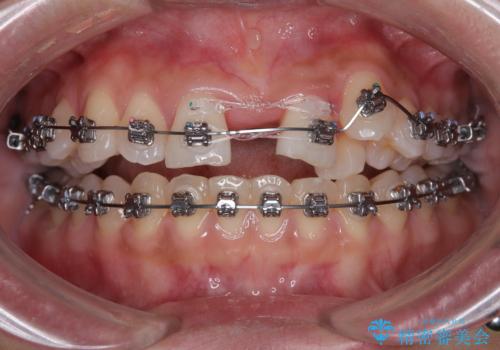

- 矯正装置

- メタルブラケット

- 治療期間

- 1年8ヶ月

- 治療回数

- 30回以上